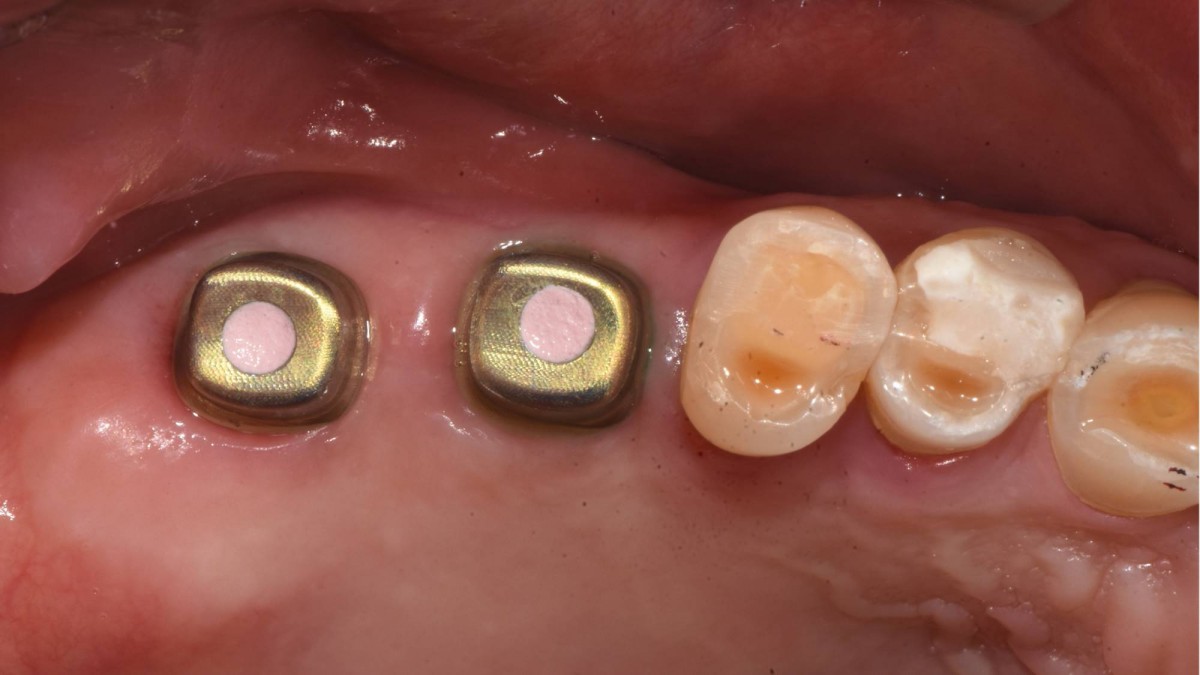

Socket Lift and Implant Placement in the right maxilla.

<GCacg> A 56-year-old male patient complained of pain in the right upper and lower jaws. And he wanted the upper first molar to be pulled out first.